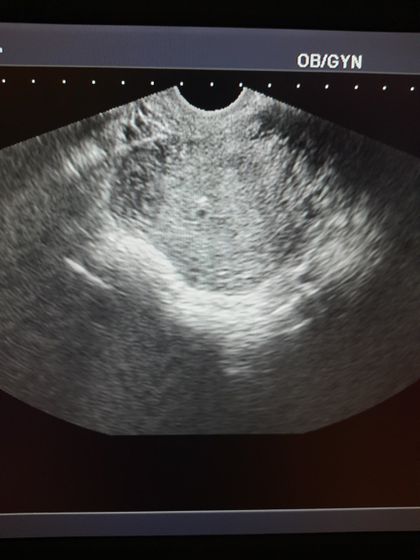

Была на УЗИ, чтоб подтвердить беременность.

Плодное яйцо всего несколько мм. Выглядит недели на 2, всего

По месячным срок уже 5 недель должен быть. Но так как после родов цикл не восстановился, то хрен знает как считать?

Ну а что не так? 5 недель акушерских, 3 эмбриональных, это при идеальном раскладе, а если овуляция позже, то и того меньше. Вы что там ещё хотели увидеть?